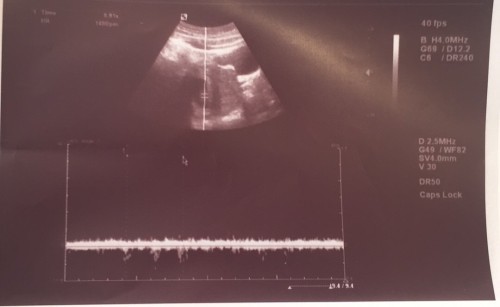

Hello everyone, 1st time preggy here nag pa check kasi ako kanina sa OB tapos sabi ng OB placenta pa lng yung nakita tapos sabi nya di sya sure kung ilang weeks na akong buntis. Sure na po ba yun na buntis talaga ako? Tuloy tuloy na po ba ito? P.S di po ako normal ang dalaw ko minsa lng po talaga ang dalaw ko

Anong LMP mo mommy? If too early, normal lang po yan. Mga 8 weeks pa nagkakaheart beat.

Ganyan din ako nung una pero makikita na yan si baby pag nasa 8 or 9 weeks ultrasound.